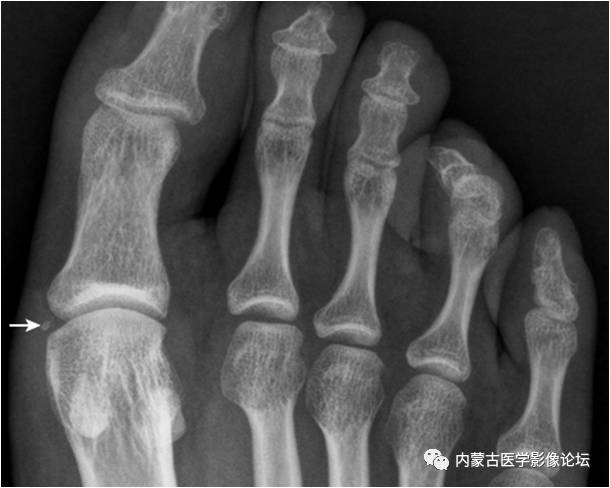

21.足趾副骨:趾跖关节内侧见点状骨性灶(箭),又称关节旁骨,一般无病理意义,但有时可引起邻近骨生长障碍和坏死。要与撕脱骨折鉴别。